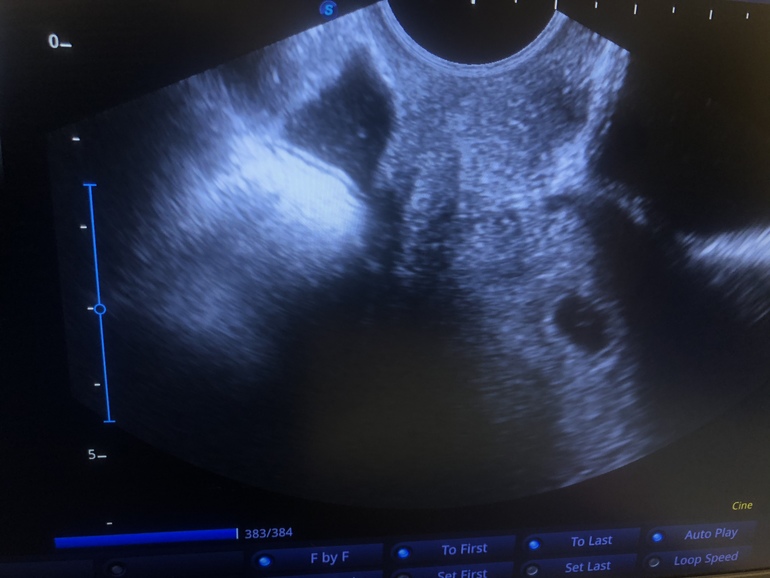

Алёна

Отличное первое фото! Прекрасно желточный мешочек видно)) через недельку уже и ктр с сердцебиением будет четко видно)) поздравляю! Пусть все у вас будет хорошо!